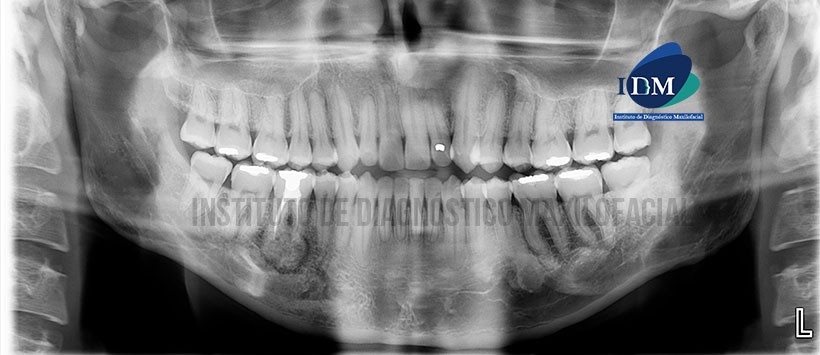

En la radiografía panorámica (Figura 1) se observa a la pieza 46 con material de obturación de conducto y una imagen radiopaca delimitada por un halo radiolúcido en zona periapical.